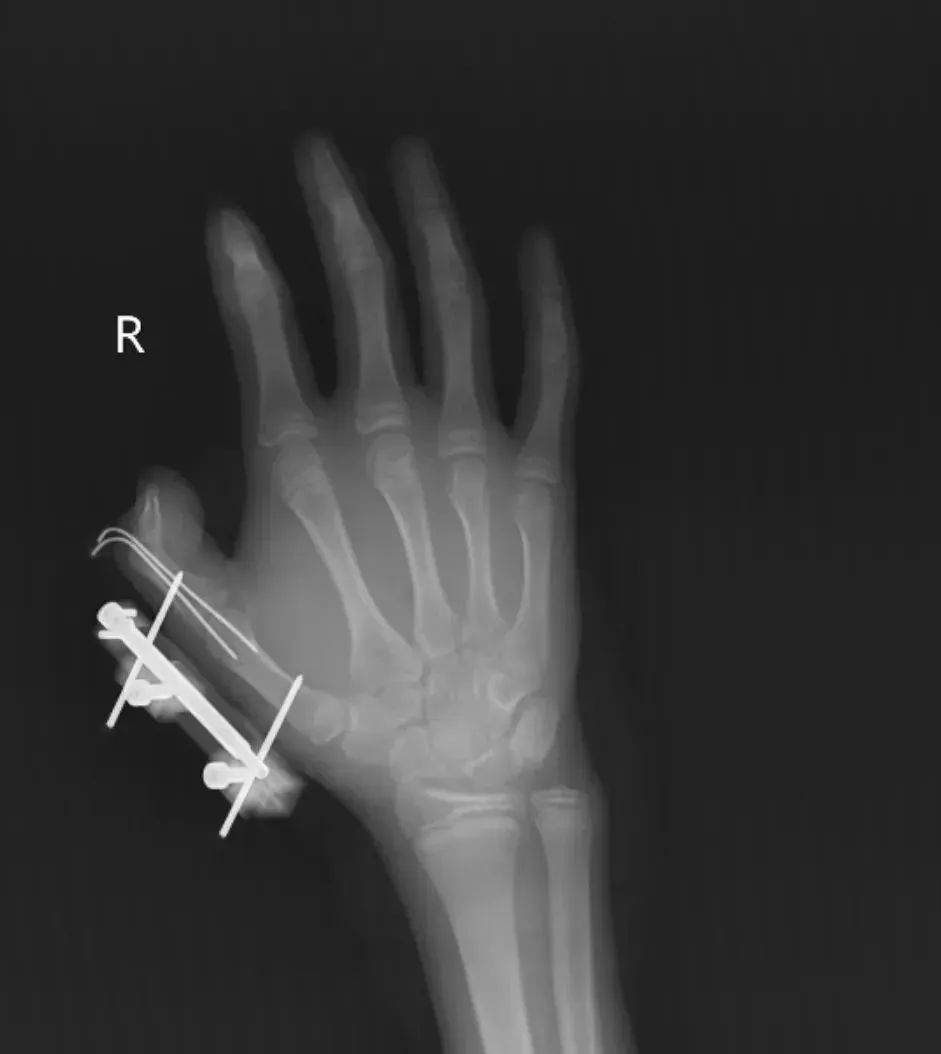

Mới đây, tại tỉnh Hồ Nam, Trung Quốc, một bé gái 14 tuổi (tên gọi là Vi Vi) phát hiện túi đá khô trong hộp kem vừa đặt mua online. Nghĩ rằng đó chỉ là loại đá bình thường, em đem túi đá khô lắc chơi trong tay. Chỉ vài giây sau, túi kín đựng đá khô bất ngờ phát nổ. Vụ nổ khiến tay phải của Vi Vi rách một đường khoảng 10cm ngay vị trí kẽ ngón cái, cơ bị đứt, lộ mô mềm, kèm theo gãy xương và trật khớp. Ngón cái hoàn toàn mất cảm giác.

Vi Vi đã được phẫu thuật giữ lại ngón tay, nhưng bác sĩ cho biết phải phục hồi chức năng dài hạn mới hy vọng lấy lại khả năng cầm nắm tinh tế.